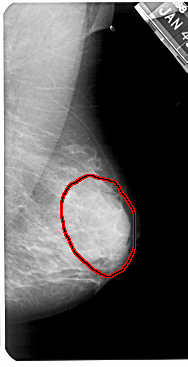

A_1425_1.RIGHT_CC

RIGHT_CC LINES 5296 PIXELS_PER_LINE 2656 BITS_PER_PIXEL 12 RESOLUTION 43.5 OVERLAY

FILE: A_1425_1.RIGHT_CC.OVERLAY

TOTAL_ABNORMALITIES 1

ABNORMALITY 1

LESION_TYPE MASS SHAPE OVAL MARGINS OBSCURED

ASSESSMENT 4

SUBTLETY 3

PATHOLOGY BENIGN

TOTAL_OUTLINES 1

BOUNDARY